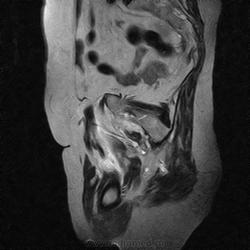

МРТ тазобедренный сустав (срочно)

Пациентка 1944г. р. Жалобы на боль области сустава в течении месяца. Температуры не отмечала. Серьезных травм со слов не было. Внешний осмотр новых данных не дал.